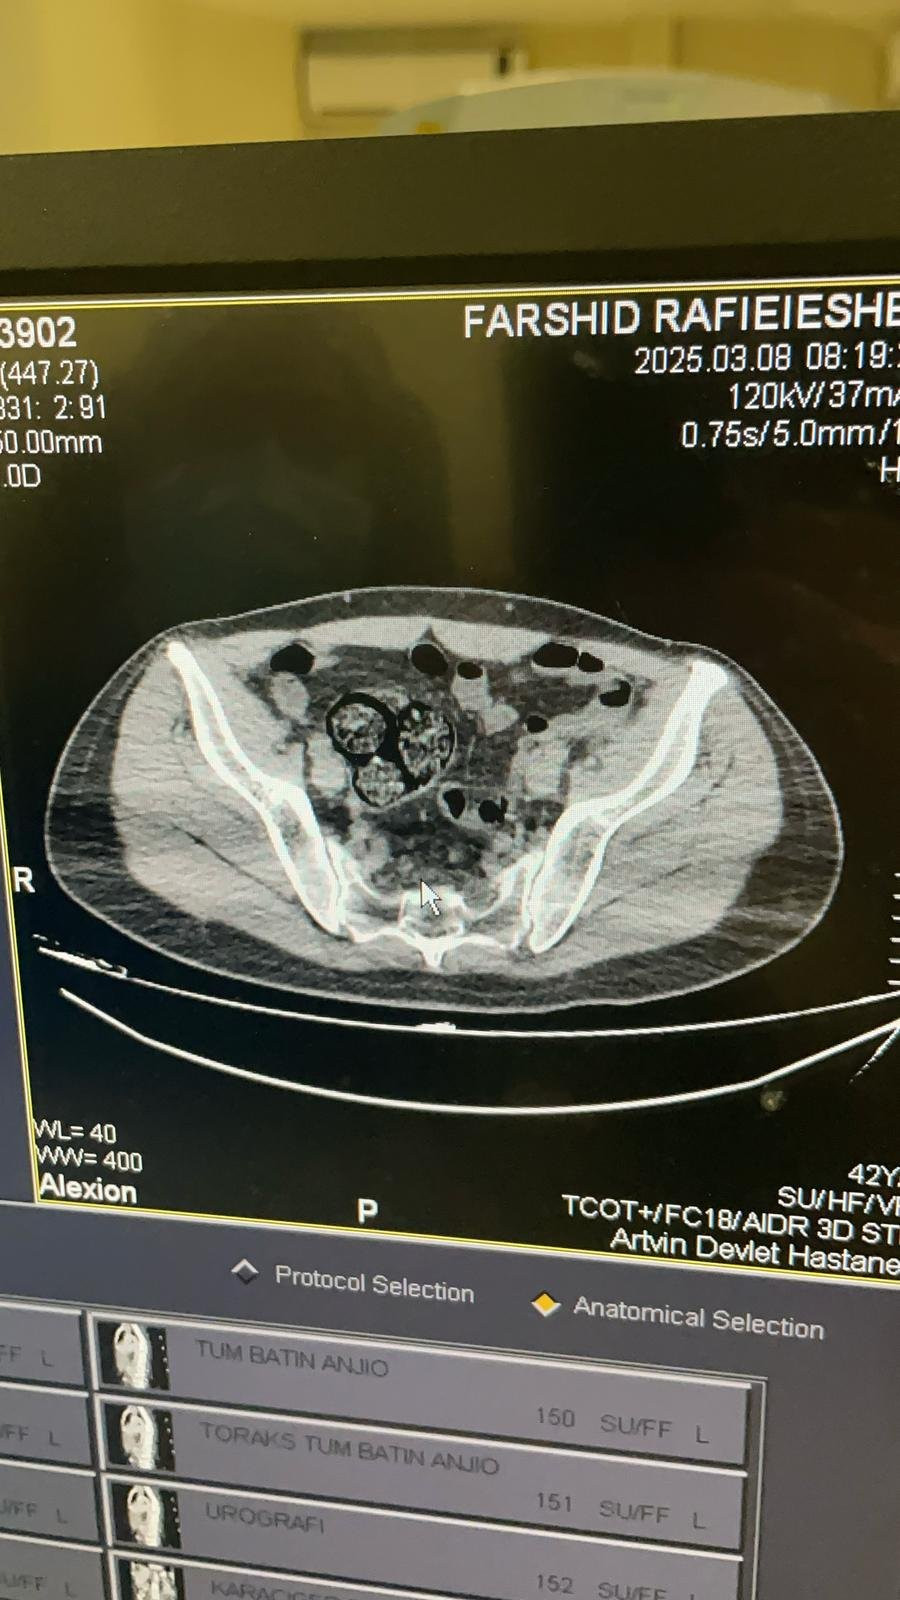

İl jandarma ekipleri, takip ettikleri İran uyruklu şüpheliyi dün saat 02.00 sıralarında Çayağzı Mahallesi'nde durdurdu. Üzerinde yapılan aramada herhangi bir olumsuzluğa rastlanmayan F.R., detaylı kontrol için hastaneye götürüldü. Artvin Devlet Hastanesi'nde tomografisi çekilen şüphelinin bağırsaklarında 10 paket halinde uyuşturucu madde taşıdığı belirlendi. Şüphelinin hayati tehlike oluşturabilecek şekilde sakladığı paketler, cerrahi müdahaleyle çıkarıldı. İncelemede paketlerin içinde toplam 350 gram metamfetamin olduğu tespit edildi.